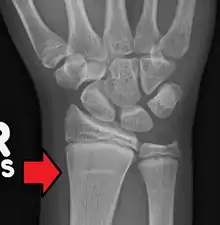

| Growth arrest lines in a child with an underlying bone disease | |

Growth arrest lines, also known as Harris lines, are lines of increased bone density that represent the position of the growth plate at the time of insult to the organism and formed on long bones due to growth arrest. They are only visible by radiograph or in cross-section. The age at which the lines were formed can be estimated from a radiograph. Harris lines are often discussed as a result of juvenile malnutrition, disease or trauma. Other studies suggest a reconsideration of Harris lines as more of a result of normal growth and growth spurts, rather than a pure outcome of nutritional or pathologic stress.[1] The lines are named after Henry Albert Harris, 1886-1968, professor of anatomy at the University of Cambridge.[2]